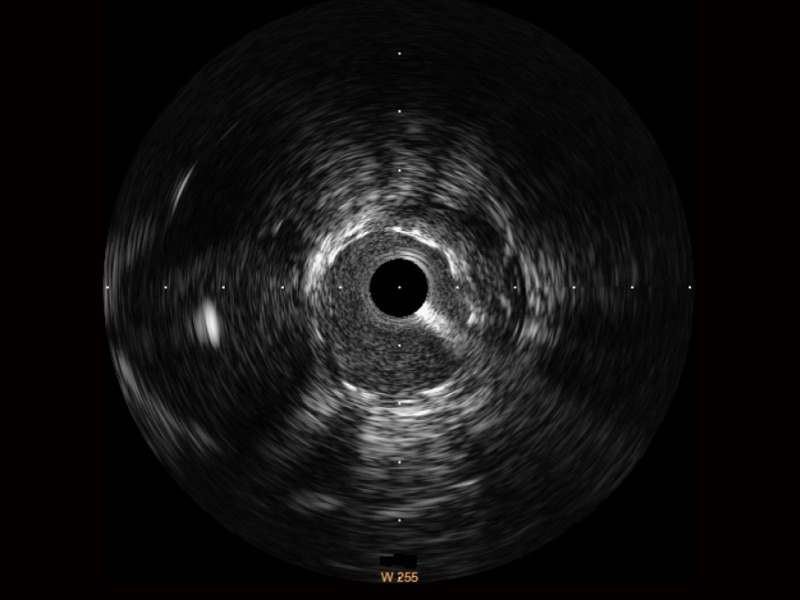

開立超寬頻成像技術(shù)覆蓋20-80MHz1或20-90MHz2頻率范圍, 提供優(yōu)異的分辨力同時也保證充足的穿透深度

1.SonoSound? Crystal導(dǎo)管

開立寬頻IVUS圖像

傳統(tǒng)IVUS圖像

對比傳統(tǒng)IVUS導(dǎo)管成像,開立寬頻IVUS圖像的近場支架梁顯影更細(xì)膩,遠(yuǎn)場中膜外血管仍清晰可辨,兼顧遠(yuǎn)中近,兼顧分辨力與穿透深度